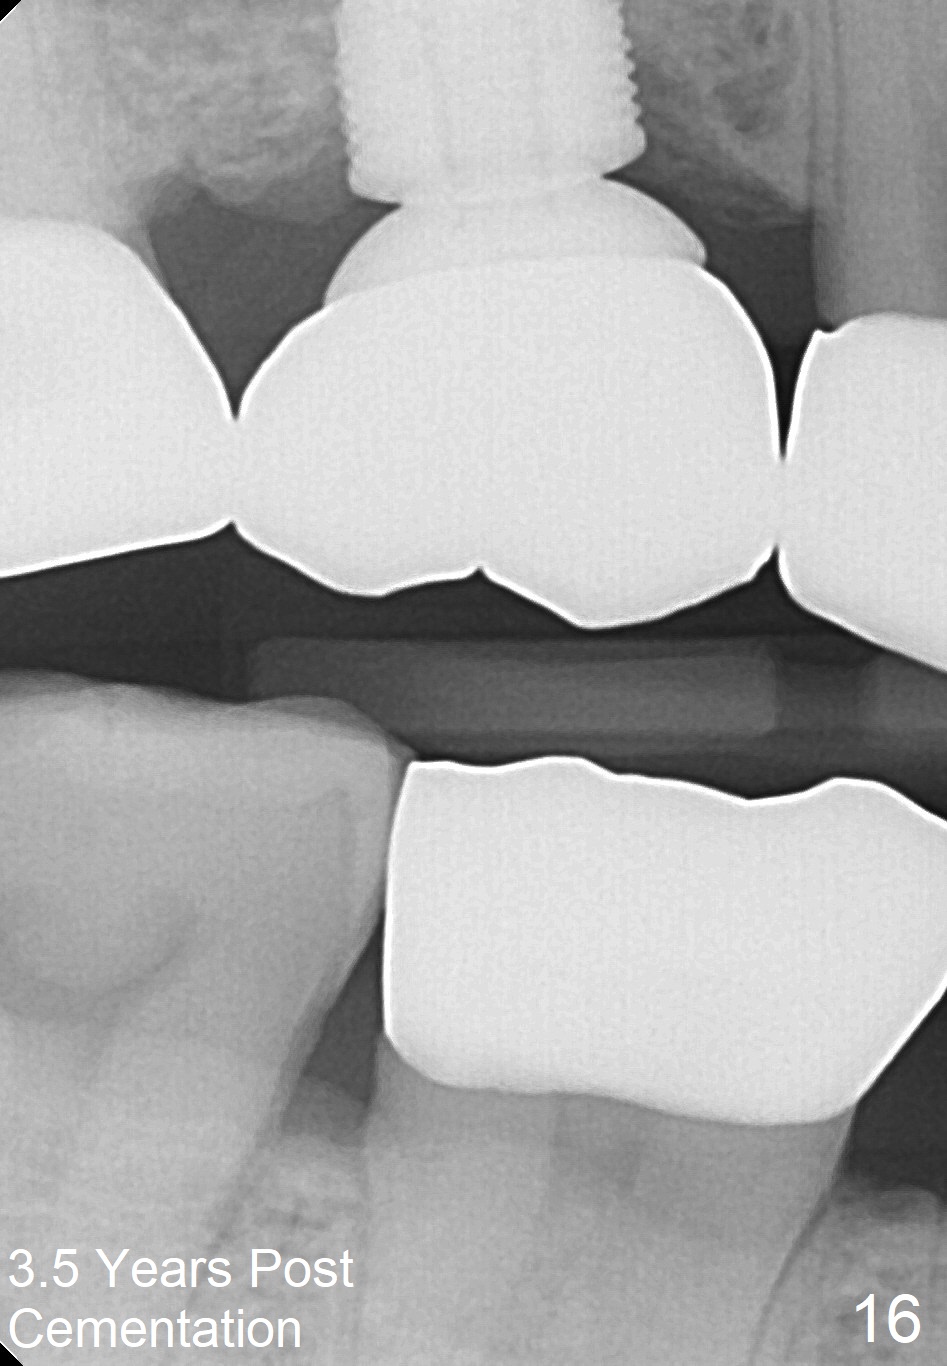

The bone density (Fig.1 white *) at the edentulous area (#3) is lower than that at the dentulous one (black *, 50 year-old man). The buccal plate is also atrophic and concave (Fig.2,3 arrowheads). A series of bone expanders are used to form osteotomy (following 1.6 mm pilot drill) at the depth of 14 mm (Fig.3 E 3.0 mm in diameter). When the last expander (4.3 mm) is removed from the osteotomy, the buccal plate appears to have been moved buccally (Fig.5 arrowheads). A 5.3x14 mm submerged implant (Fig.6 I) is placed with insertion torque >35 Ncm. The buccal plate seems to improve following placement of an 8.2 mm healing abutment and suturing (Fig.7). No bone graft is used. The buccal plate remains normal 12 days postop (Fig.8). It is slightly concave 3 months postop (Fig.9) with minimal bone resorption at the crest (Fig.10 (H: healing abutment),11 (A: cemented abutment). Nine months post cementation (12 months postop), bone resorption at the crest remains minimal (Fig.12) while the buccal plate (Fig.13 *) at #3 remains strong. Bone loss appears not to get worse 22 months post cementation (Fig.14). Soft and hard tissues remain healthy around the implant crown 3 years (Fig.15) and 3.5 years (Fig.16,17) post cementation.

In brief, bone expanders or osteotomes can be used for bone expansion and condensation to improve primary stability of implant placement. No bone graft appears to be needed. The buccal concavity remains minimal 6 years post cementation (Fig.18). In fact he is a bruxer with torus palatinus (Fig.19). The bridge of #9-11 is loose because of subgingival fracture of the abutment of #11 for 2.5 years (Fig.20).